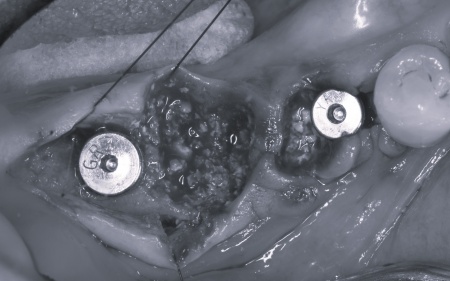

①入れ歯 ②インプラント それぞれのメリットとデメリットをお伝えしたところ、患者様は「できるだけ違和感がなく噛めるようになりたい。またなるべく短期間で治療を終えたい」と希望されたため、抜歯と同時にインプラントを埋め込む抜歯即時埋入法を提案し、同意いただきました。 まず、右下奥歯(第2小臼歯、第1大臼歯)を抜きます。 抜歯後にできた穴とインプラントの間には隙間が生じるため、骨の再生を助ける目的で骨補填材を使用しながら、丁寧に縫合しました。 3ヶ月後、インプラントと骨がしっかりと結合したことが確認できたため、被せ物を作製するための型取りを行います。 後日、完成した被せ物を装着し、見た目や噛み合わせに問題がないことを確認して、治療を終了しています。 |